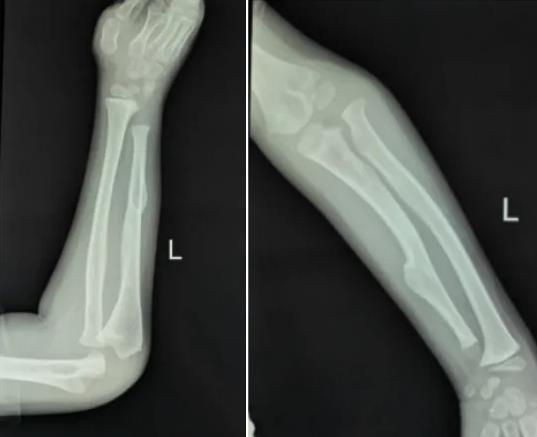

遗传性骨软骨瘤病(Hereditary Multiple Osteochondromas, HMO)是一种罕见的常染色体显性遗传疾病,以骨骼表面多发性骨软骨瘤形成为特征。该病若累及前臂,可导致桡骨或尺骨畸形,进而影响关节功能、肢体长度,甚至压迫神经血管。患儿小马(化名)的病情正是如此——其左前臂严重畸形,若不及时干预,未来可能面临肢体功能障碍、骨骼发育停滞等严重后果。

前臂畸形

吴立文医生在接诊后指出:“儿童骨骼系统处于快速发育阶段,任何畸形都可能被放大。尤其是前臂的复杂结构涉及骨骼、韧带及神经,手术需在矫正畸形的同时保护骨骺,这对术者的解剖学功底和手术精度要求极高。”

软骨瘤形成,尺骨短缩,桡骨头脱位